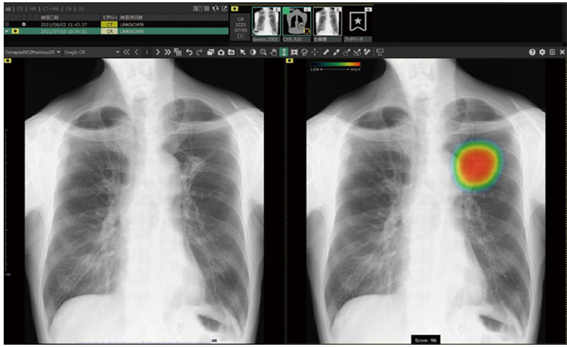

○ レントゲン検査(X線検査)

レントゲン検査は、X線(放射線)を体に当てて体内の様子を画像化する検査です。切らずに体内の病気や怪我を発見することができ、低侵襲で高い診断価値を得ることができます。

また当クリニックでは、胸部レントゲンの読影にAIでサポートする機器(富士フィルム社 CXR-AID)を導入しました。CXR-AIDは、胸部X線画像を自動解析し、病変の存在が疑われる領域を検出・マーキング・見落とし防止を支援するシステムです。医療AI技術を適切に活用し、より良い医療の提供を目指してまいります。